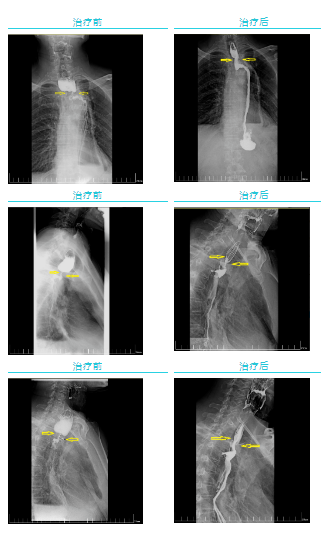

經(jīng)過一個(gè)周期的放療,李先生明顯感受好多了,可以正常吃飯喝水。食管鋇餐造影顯示,食管吻合口區(qū)腫塊明顯縮小,食管狹窄減輕。